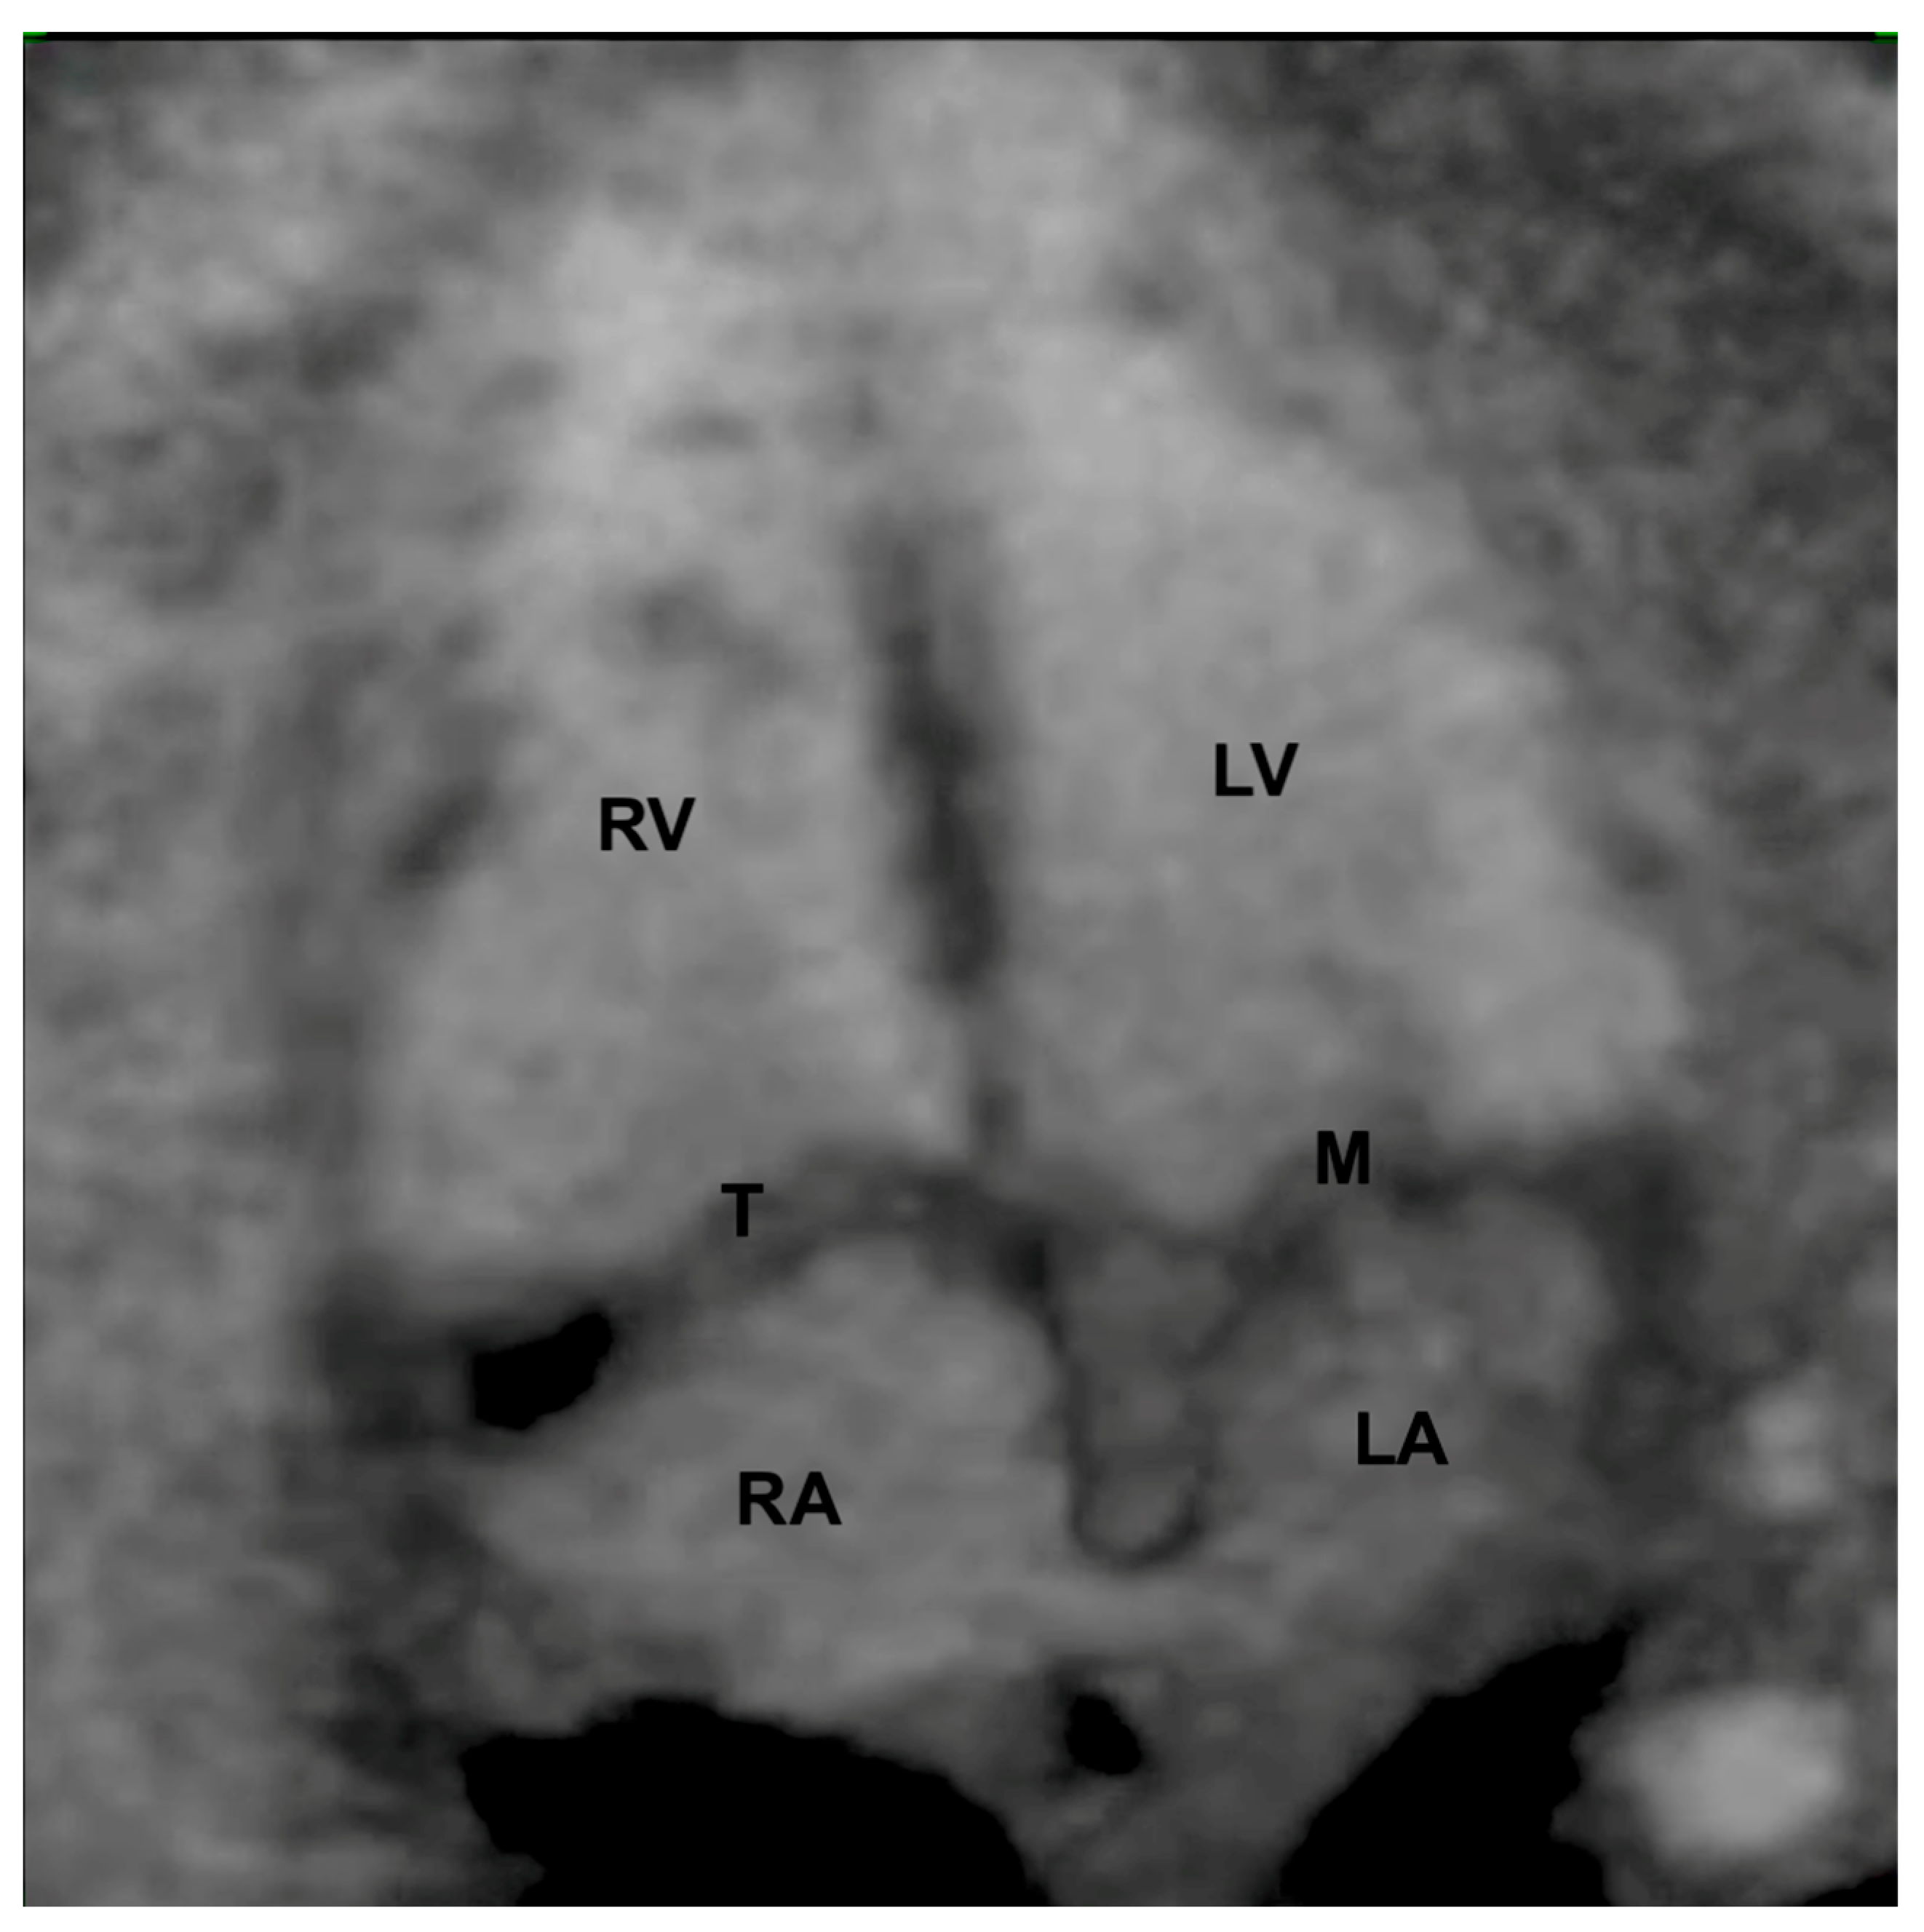

7. Isomerism

8. Atrioventricular Septal Defect